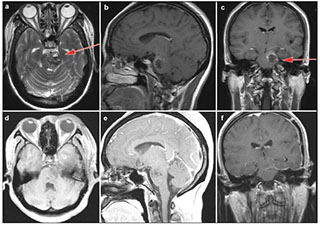

20170712151439 Figure 4 Case 2: Left anterolateral medullary cavernous malformation. Axial T2-weighted (a) and sagital T1-weighted (b) showed the location of the lesion. Axial T1-weighed (c) and enhanced sagittal T1-weighted (d) postoperative within 72 h showed that the lesion was totally resected. Enhanced axial T1-weighted (e) and enhanced sagittal T1-weighted (f) at 5-month postoperative follow-up. Red arrow showed the entry approach (retrosigmoid approach).

20170712151506 Figure 5 Case 3: Cavernous malformation in the left pons and lower midbrain. T2-weighted (a), enhanced sagittal T1-weighted (b) and enhanced coronal T1-weighted (c) demonstrated the location of the cavernous malformation. Enhanced axial T1-weighted (d) and sagittal T1-weighted (e) postoperative within 72 hours showed that the lesion was totally resected. Enhanced coronal T1-weighted (f) showed no recurrence after 3 months follow-up. Red arrow showed the entry approach (subtemporal approach).